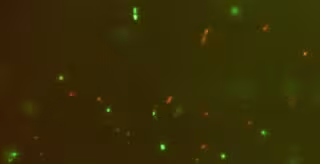

Microbiota fecal

El trabajo, que se ha publicado en la revista 'Scientific Reports', ha partido de estudios previos en los que ya habían demostrado las 'diferencias significativas' entre poblaciones microbianas en las heces de personas sanas e individuos con lupus, que se manifestaban por un descenso de la ratio Firmicutes/Bacteroidetes. A través de un método que permite separar la microbiota intestinal del resto de contenido fecal, han añadido bacterias de cepas de 'Bifidobacterium bifidum', 'Ruminococcus obeum' y 'Blautia coccoides'.